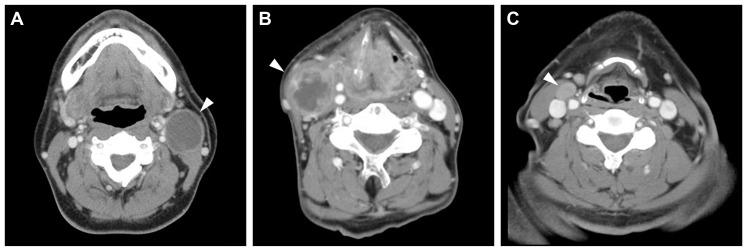

The clinical significance of human papillomavirus (HPV) in neck node metastasis from cancer of unknown primary (CUP) is not well established. We aimed to address the relationship of HPV status between node metastasis and the primary tumor, and also the relevance of HPV status regarding radiographically detected cystic node metastasis in head and neck squamous cell carcinoma (HNSCC) and CUP. HPV DNA was examined in 68 matched pairs of node metastasis and primary tumor, and in node metastasis from 27 CUPs. In surgically treated CUPs, p16 was examined immunohistochemically. When tonsillectomy proved occult tonsillar cancer in CUP, HPV DNA and p16 were also examined in the occult primary. Cystic node metastasis on contrast-enhanced computed tomography scans was correlated with the primary site and HPV status in another series of 255 HNSCCs and CUPs with known HPV status. Node metastasis was HPV-positive in 19/37 (51%) oropharyngeal SCCs (OPSCCs) and 10/27 (37%) CUPs, but not in non-OPSCCs. Fluid was collected from cystic node metastasis using fine needle aspiration in two OPSCCs and one CUP, and all fluid collections were HPV-positive. HPV status, including the presence of HPV DNA, genotype, and physical status, as well as the expression pattern of p16 were consistent between node metastasis and primary or occult primary tumor. Occult tonsillar cancer was found more frequently in p16-positive CUP than in p16-negative CUP (odds ratio (OR), 39.0; 95% confidence interval (CI), 1.4-377.8; P = 0.02). Radiographically, cystic node metastasis was specific to OPSCC and CUP, and was associated with HPV positivity relative to necrotic or solid node metastasis (OR, 6.2; 95% CI, 1.2-45.7; P = 0.03). In conclusion, HPV status remains unchanged after metastasis. The occult primary of HPV-positive CUP is most probably localized in the oropharynx. HPV status determined from fine needle aspirates facilitates the diagnosis of cystic node metastasis.

人乳头瘤病毒 (HPV) 在不明原发灶 (CUP) 颈部淋巴结转移中的临床意义尚未明确。我们旨在研究 HPV 状态与淋巴结转移和原发灶的关系,以及 HPV 状态与头颈部鳞状细胞癌 (HNSCC) 和 CUP 中影像学检测到的囊性淋巴结转移的相关性。在 68 对淋巴结转移和原发肿瘤以及 27 例 CUP 的淋巴结转移中检测了 HPV DNA。在手术治疗的 CUP 中,用免疫组化法检测了 p16。当扁桃体切除术证实 CUP 中有隐匿性扁桃体癌时,也在隐匿性原发灶中检测了 HPV DNA 和 p16。在另一组 255 例已知 HPV 状态的 HNSCC 和 CUP 中,对比增强 CT 扫描显示囊性淋巴结转移与原发部位和 HPV 状态相关。19/37(51%)例口咽鳞癌(OPSCC)和 10/27(37%)例 CUP 的淋巴结转移为 HPV 阳性,而非 OPSCC 则无。在 2 例 OPSCC 和 1 例 CUP 中,使用细针抽吸从囊性淋巴结转移中收集了液体,所有液体采集均为 HPV 阳性。HPV 状态,包括 HPV DNA、基因型和物理状态以及 p16 的表达模式,在淋巴结转移和原发或隐匿性原发肿瘤之间均一致。p16 阳性 CUP 中隐匿性扁桃体癌的检出率高于 p16 阴性 CUP(比值比 (OR),39.0;95%置信区间 (CI),1.4-377.8;P=0.02)。影像学检查显示,囊性淋巴结转移是 OPSCC 和 CUP 的特征,与坏死或实性淋巴结转移相比,与 HPV 阳性相关(OR,6.2;95%CI,1.2-45.7;P=0.03)。总之,HPV 状态转移后保持不变。HPV 阳性 CUP 的隐匿性原发灶最有可能位于口咽。从细针抽吸物中确定 HPV 状态有助于诊断囊性淋巴结转移。